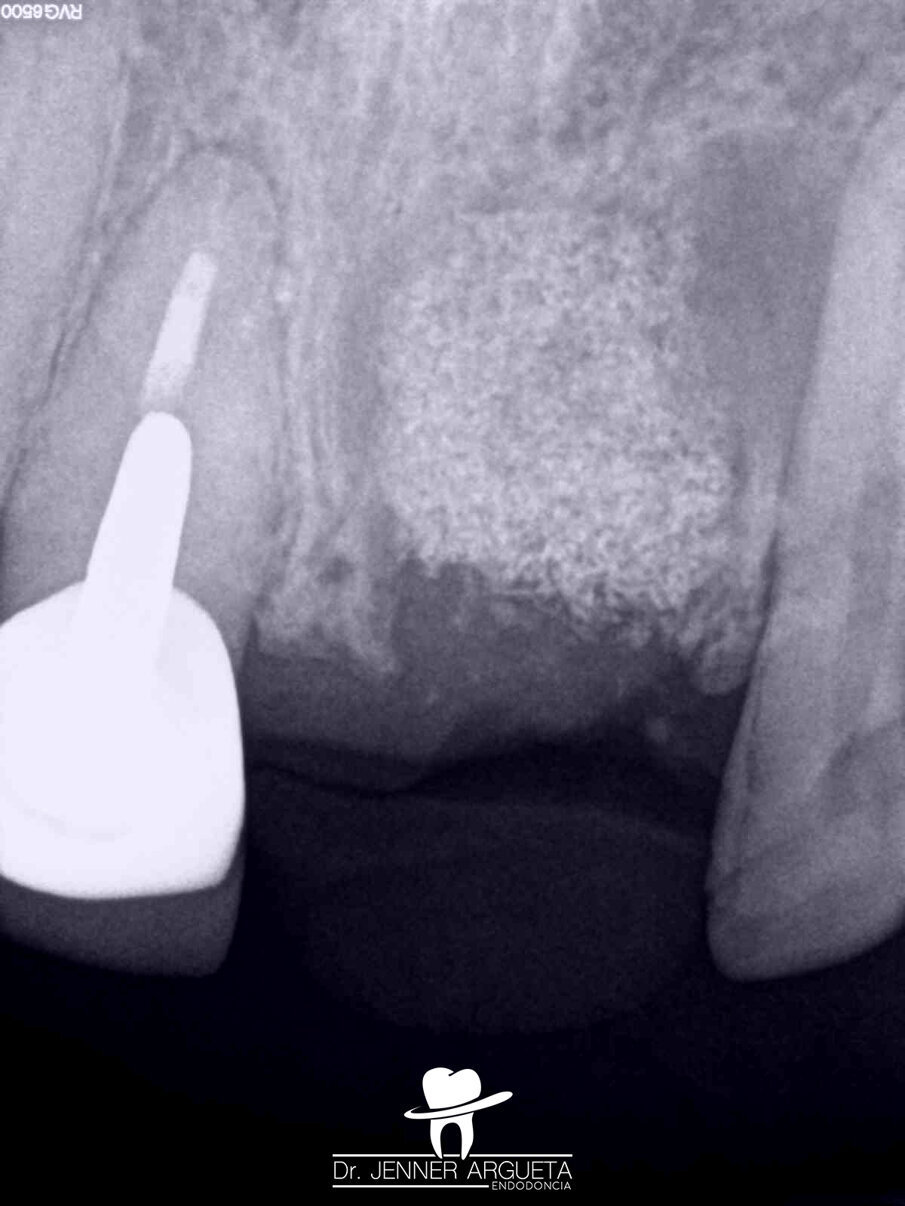

A 35-year-old male patient reported pain affecting the central incisors. Upon clinical examination, an acute periapical abscess was detected; radiographically, resorptive radicular defects in tooth #11 were observed. The patient reported a traumatic injury in the area several years before. The established diagnosis was pulp necrosis and an acute periapical abscess.

Figs. 6a–c: Radiographic sequence of the treatment performed in tooth #11. Initial radiograph. The root resorption and lateral radiolucent area were evident (a). Working length measurement at the level of the resorption (b). Root resorption repair with a calcium silicate-based material (c).

Figs. 7a–c: Radiographic sequence of the treatment performed in tooth #11. Initial radiograph. The root resorption and lateral radiolucent area were evident (a). Master cone fitting at the level of the complete working length (b). Completed root canal therapy (c).

Fig. 8: Radiographic sequence of the treatment performed in tooth #11. Initial radiograph. The root resorption and lateral radiolucent area were evident (a). Completed root canal therapy (b). Three-year follow-up radiograph showing complete healing of the lateral radicular radiolucent area and the correct sealing of the resorption (c).

During the first appointment for root canal therapy, it was not possible to reach the complete length of the root canal, because the files tended to go inside of the mesial resorption. It was decided to seal the resorptive defect (Fig. 6a–c) using CeraSeal sonically activated using the EQ-S device (Meta Biomed; see video below).

At the second appointment, the material placed at the resorption was completely hard. That hard barrier allowed the file to pass through the entire length of the physiological root canal. The root canal therapy was finished using CeraSeal as the endodontic sealer (Fig. 7a–c). The three-year follow-up radiograph showed complete healing of the lateral radicular radiolucent area (Fig. 8a–c).